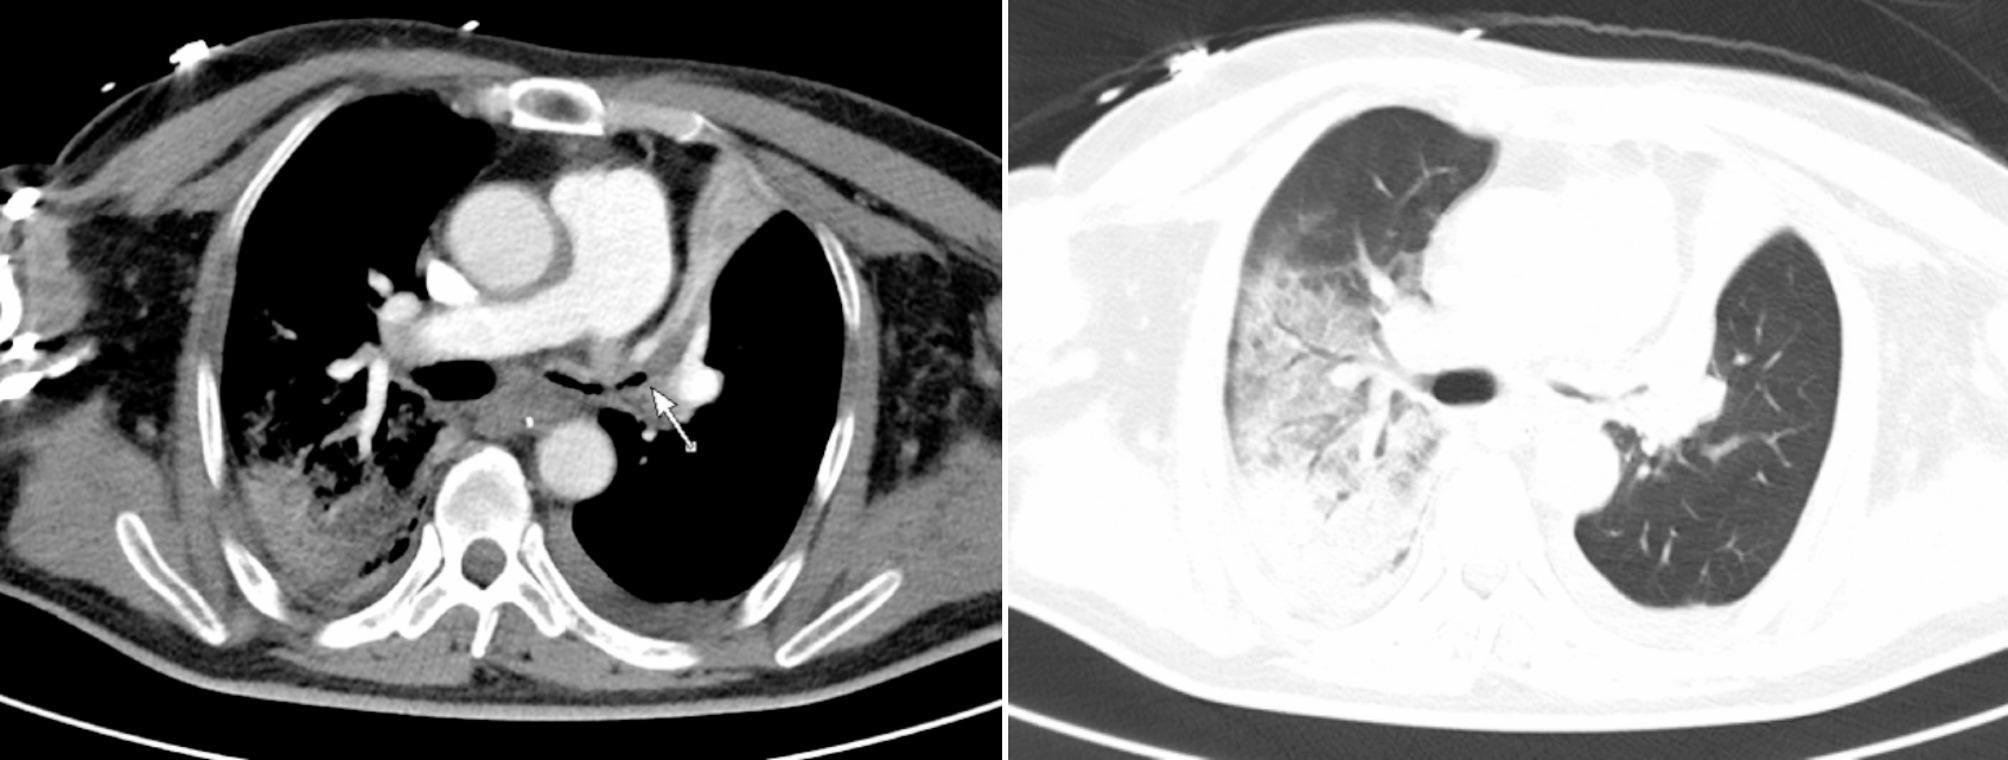

Case presentation: We report the first case of SVC syndrome in an adult patient with pre-existing SVC angulation, exacerbated by cannula placement during VV ECMO therapy. Serial venous-phase chest CT scans (pre-ECMO and during ECMO support) demonstrated progressive luminal narrowing at the cannula tip site, correlating with clinical manifestations of SVC obstruction. The patient was successfully weaned from VV ECMO, achieved complete resolution of SVC syndrome symptoms, and was discharged without neurological sequelae.

Conclusions: This case provides definitive imaging evidence that ECMO cannula placement alone can induce acute SVC stenosis in patients with pre-existing vascular tortuosity. Our findings strongly advocate for pre-procedural vascular imaging assessment and real-time monitoring during ECMO support to mitigate this life-threatening complication.